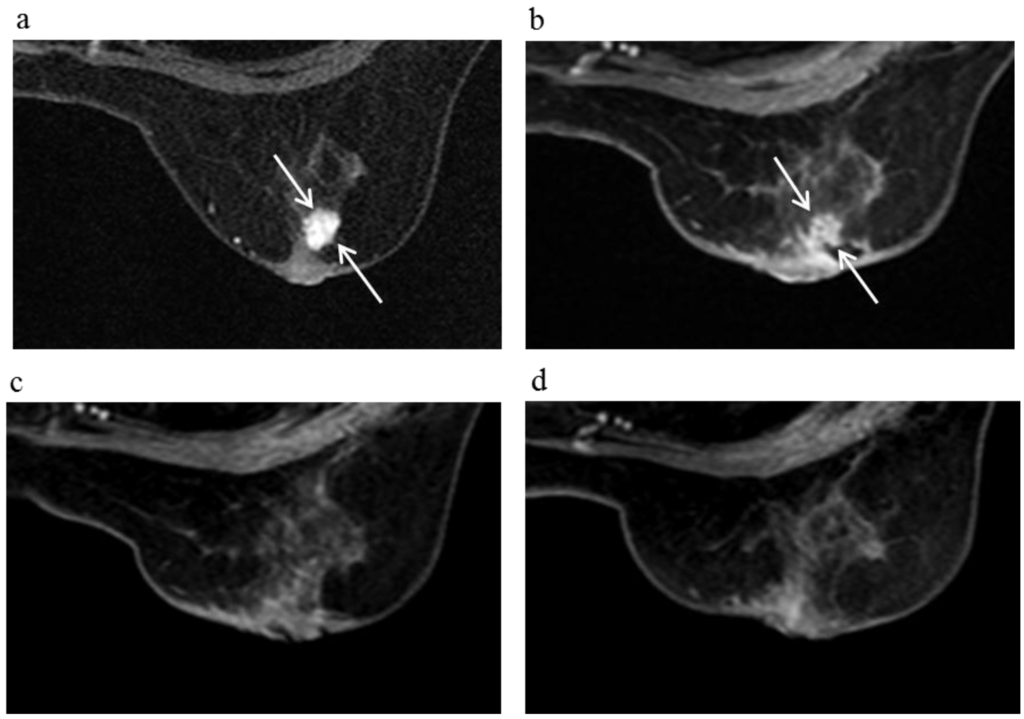

Figure 3.

A 81-year-old female (case 7 in Table 1, Table 2 and Table 3) with right breast cancer (cT2N1M0). CE breast MRI, PET-CT and mammography revealed a breast tumor before KORTUC II therapy, the region of tumor was 25 mm in large diameter (a–c); At the initial examination after the completion of KORTUC II treatment, the tumor was undetectable on PET-CT and mammography (e,f); On the other hand, the residual tumor was still recognized on breast CE MRI ((d): arrows). However, complete response was eventually achieved and no recurrence was identified on final examinations of all of these three diagnostic modalities (g–i).